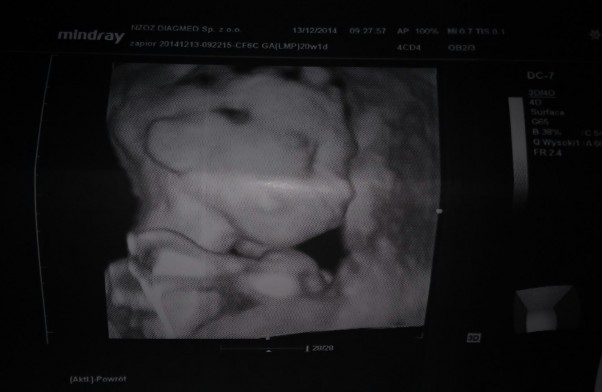

Nasza córeczka w końcu przyjdzie na świat :) czekamy z niecierpliwoscią !